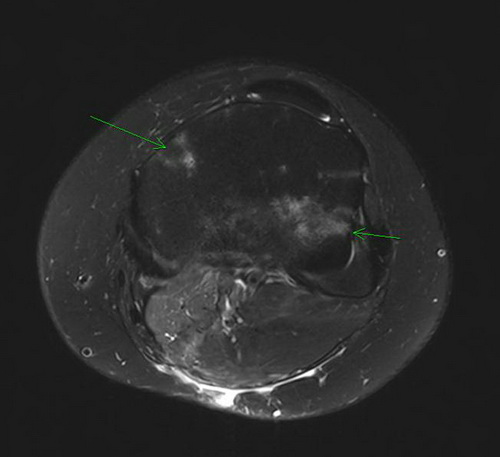

MRT

Axial T2 fs 448i 3mm p2

Die Verlaufskontrolle via MRT des Kniegelenks links sollte im ersten Jahr in dreimonatigen Abständen erfolgen. Die Lunge soll mittes Röntgen-Thorax a.p. ebenfalls in 3 monatigen Abständen nachkontrolliert werden.